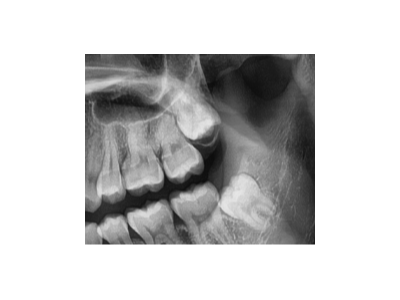

根管治療的全過程主要包括術(shù)前檢查和診斷、局部麻醉、開髓、根管預(yù)備、根管消毒,以及根管充填、術(shù)后修復(fù)。1、術(shù)前檢查與診斷:患者先到口腔科進行全面檢查,包括患牙的齲壞程度、牙髓活力測試、叩診等,以確定患牙…